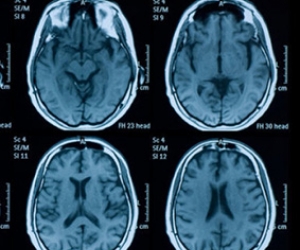

نشرت صحيفة "هافنغتون بوست"، بنسختها البريطانيّة، نتائج تجربة أجراها باحثون من جامعات "فاندربيلت"، وجامعة "فرجينيا التقنية"، وجامعة "بيل" الأميركيّة، والتي أفادت بأنّه من الممكن الكشف عن "حالة المعرفة"، لدى المشتبهين، إذا كانوا قد ارتكبوا الجرم بشكل متعمد أم لا.

وقال الباحثون في نتائج تجربتهم، إنّه أصبح من الممكن الكشف عما إذا كانت الجريمة متعمدة أم لا، من خلال دراسات أجريت على الدماغ البشري، وهو ما يمكن أن يساعد المحكمة، إذ ليس من السهل دائمًا التمييز بين الحالتين.

وكانت القائمون على التجربة، قد طلبوا من 40 مشاركًا، أن يقرروا إذا ما كانوا سيحملون الحقيبة الأولى أو الثانية، حيث استطاع العلماء، التنبؤ من خلال التصوير الدماغي والتعلم الآلي، إذا ما كان المشتركون على علم بما تحتوي الحقيبة أم لا.

وتساءل مونتاغيو، عن شكل النتائج في حال إجراء هذه التجارب على أربعة آلاف شخص، بدلًام ن 40، كما حدث فيهذه التجربة، مشيرًا إلى الدوائر العصبية المسؤولة عن اتخاذ القرارات في الدماغ.